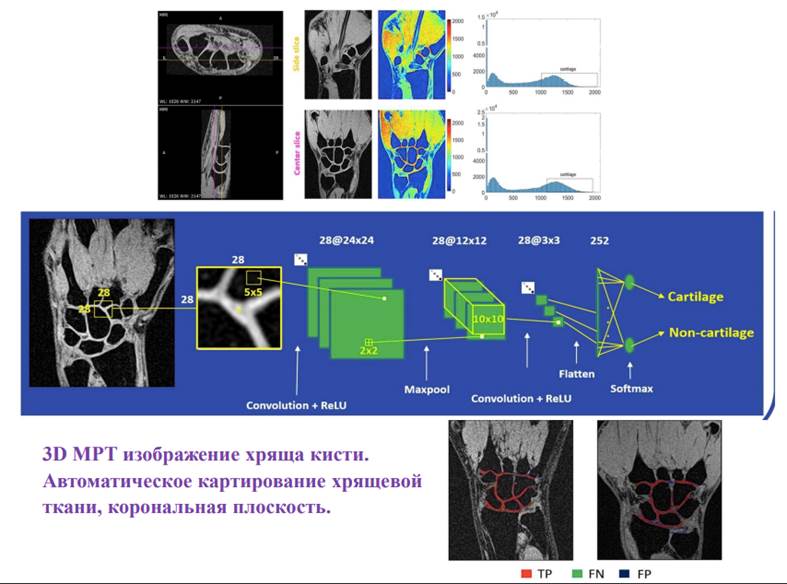

5. Проводятся совместные исследования в области искусственного интеллекта – разработка глубокой нейронной сети для полной автоматической сегментации хрящевой ткани кистевого сустава, которая позволит измерять его толщину, объём, локализацию и степень выраженности патологических изменений, крайне сложные для визуальной оценки дажеопытным специалистом лучевой диагностики. Это имеет колоссальное практическое значение для выбора терапевтической тактики, контроля течения заболевания, но особенно – для выявления заболевания на ранних стадиях, при стертой картине клинико-лабораторных данных.

Иллюстрация алгоритма сегментации хрящевой ткани.

Nikita Vladimirov, Ekaterina Brui, Anatoliy Levchuk, Walid Al-Haidri, Vladimir Fokin, Aleksandr Efimtcev, David Bendahan. CNN-based fully automatic wrist cartilage volume quantification in MR images: A comparative analysis between different CNN architectures. Magnetic Resonance in Medicine. 2023; 1-15. DOI:10.1002/mrm.29671. IF 3,737.